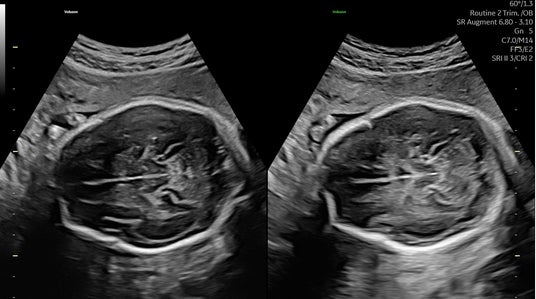

減衰を補うAugmentと、音響陰影を補うShadow Reductionを使用した画像(off/on)